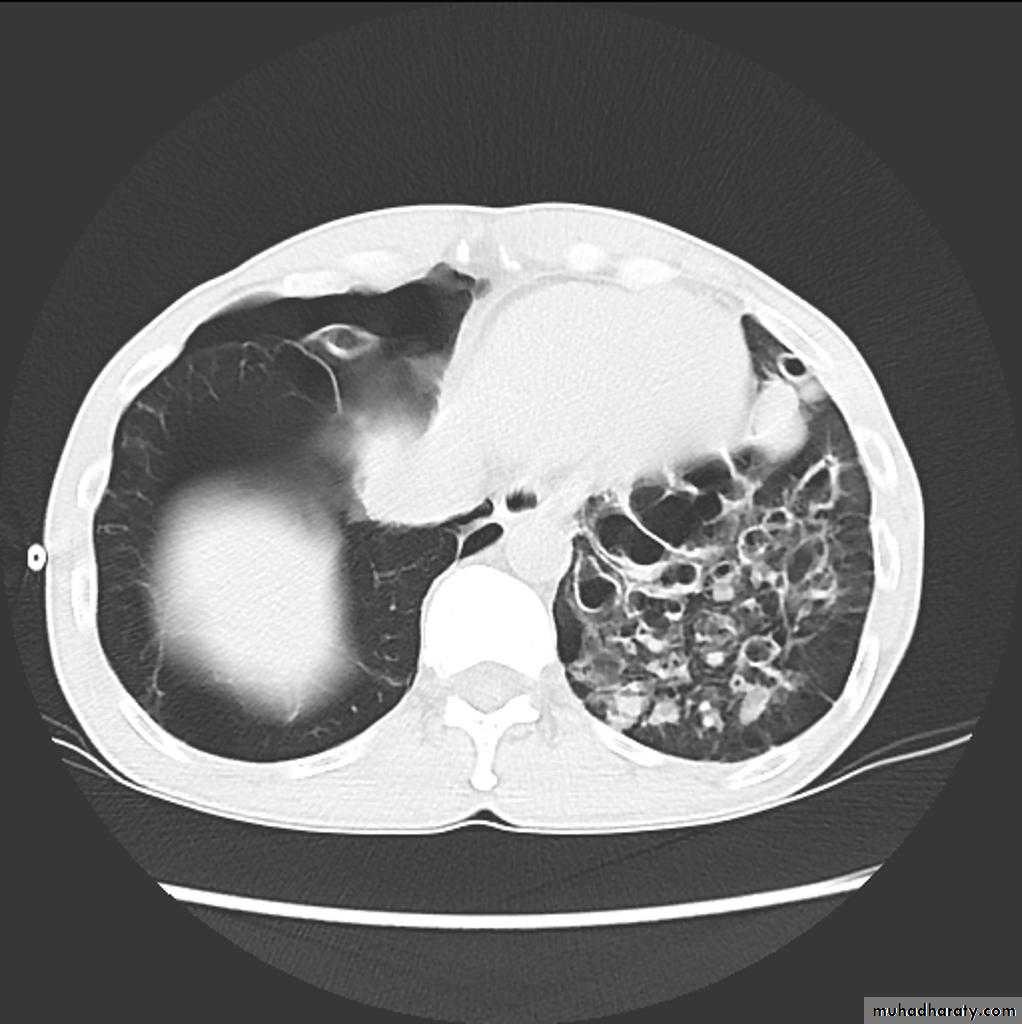

Bronchiactasis

Bronchiectasis refers to abnormal dilatation of the bronchial tree and is seen in a variety of clinical settings. CT is the most accurate modality for diagnosis. It is largely considered irreversibleCauses of bronchiactasias very important to consider

Plain radiograph

Chest x-rays are usually abnormal

1. Tram-track opacities are seen in cylindrical bronchiectasis, and

2. air-fluid levels may be seen in cystic bronchiectasis.

Honey comb shadow

3.Overall there appears to be an increase in bronchovascular markings, and bronchi seen end on may appear as ring shadows .

4.Pulmonary vasculature appears ill-defined, thought to represent peri bronchovascular fibrosis .